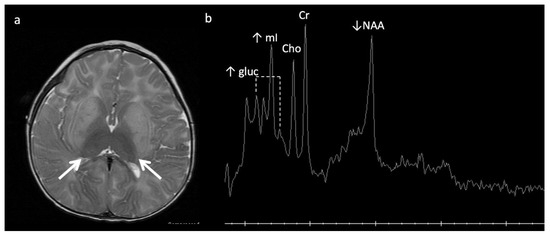

Lysosomal storage disease: GM2 gangliosidoses, including Tay-Sachs disease and Sandhoff disease (Figure 5), can show characteristic T2 hypointensity in the ventral thalami and T2 hyperintensity in the basal ganglia and dorsal thalami [28]. Krabbe disease (Figure 6) may show diffuse thalamic T2 hypointensity extending to the corticospinal tracts, as well as signal abnormalities in the cerebral and cerebellar white matter, especially the dentate hila and posterior cerebral white matter (centrifugal and posteroanterior gradient often with a tigroid pattern) and variable enlargement of the optic nerve and chiasm due to accumulation of globoid cells; MR phenotypes vary with age [3,8,10,29]. Post-contrast enhancement of multiple cranial nerves and the cauda equina is also characteristic. Metachromatic leukodystrophy (Figure 7) and Krabbe disease may have overlapping imaging features; however Krabbe disease typically spares the callosal genu and more often involves the internal capsules and brainstem [30]. Neuronal ceroid lipofuscinosis may also demonstrate thalamic T2 hypointensity, with cortical atrophy as another prominent feature [9].

Figure 5.

Eleven-month-old boy with Sandhoff disease (GM2 gangliosidosis), presenting with global developmental delay, hypotonia, and hyperreflexia. Axial T2WI (a) show abnormal hypointensity in the lateral thalami (arrows) typical of a lysosomal storage disorder, and hyperintensity consistent with edema in the bilateral basal ganglia and cerebral white matter. (b) SV-MRS over the basal ganglia shows reduced NAA and elevated mI—consistent with neuronal–axonal damage. Glucose (gluc peaks at 3.4, 3.8 ppm) is prominent, suggesting altered glucose (energy) metabolism.